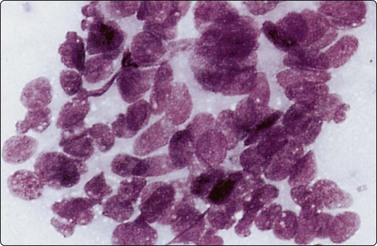

Benign prostatic hyperplasia (BPH) (Fig. 13.2)4,5,34,36,37,39

Fig. 13.2 Prostate, benign hyperplasia

Honeycomb-like sheets of uniform glandular epithelial cells; note visible cell borders and coarse cytoplasmic granules in A (A, DQ; B, Pap, HP).

Cohesive monolayered sheets of glandular epithelial cells can be quite large with distinct boundaries; most cells are seen on end and appear polygonal with centrally placed nuclei. The abundant pale cytoplasm and the distinct cell membranes give the sheet a honeycomb appearance (Fig. 13.2A,B). Only at the periphery are some cells seen in profile as columnar.

The main criteria of benignity are the uniform distribution of nuclei within monolayered sheets, distinct cell membranes, low N : C ratio and intracytoplasmic secretory granules (Fig. 13.2A). The granules stain dark magenta with DQ but are less conspicuous in alcohol-fixed Pap-stained smears. Although granules are not present in all benign epithelial cells, they are rarely present in carcinoma cells and absent in epithelial cells from rectal mucosa.